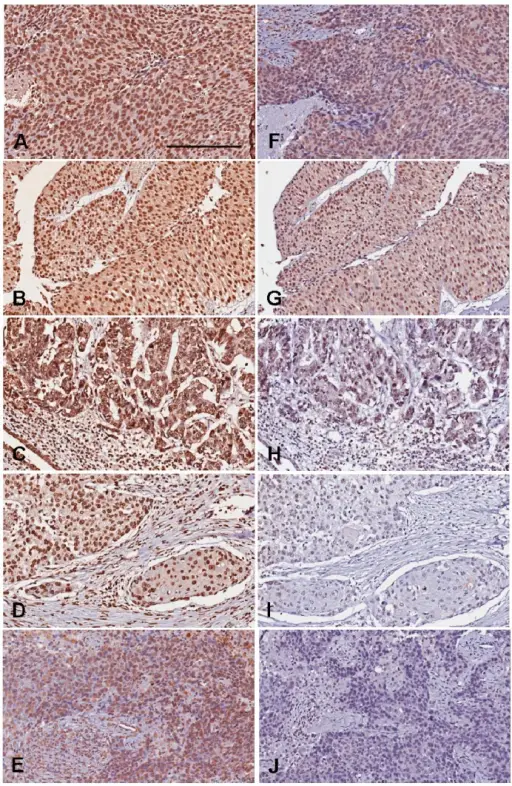

Urothelial Carcinoma

Urothelial carcinoma is also known as transitional cell carcinoma.

The epithelial lining of the renal pelvis, ureter, bladder, or urethra is the source of this malignant tumor.

Urothelial carcinoma is the most typical type of bladder cancer.

Urothelial carcinoma arises via two distinct pathways:

- Flat

- Papillary

Flat urothelial carcinoma is characterized by the invasion of a high-grade flat tumor and is associated with p53 early mutations.

Papillary urothelial carcinoma initially appears as a low-grade papillary tumor, advances to a high-grade papillary tumor, then invades, and is not linked to early p53 mutations.